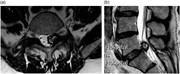

BRAF V600D mutation in a paediatric high-grade glioma

Aisling Ní Nualláin and others

Journal of Surgical Case Reports, Volume 2016, Issue 10, October 2016, rjw150, https://doi.org/10.1093/jscr/rjw150